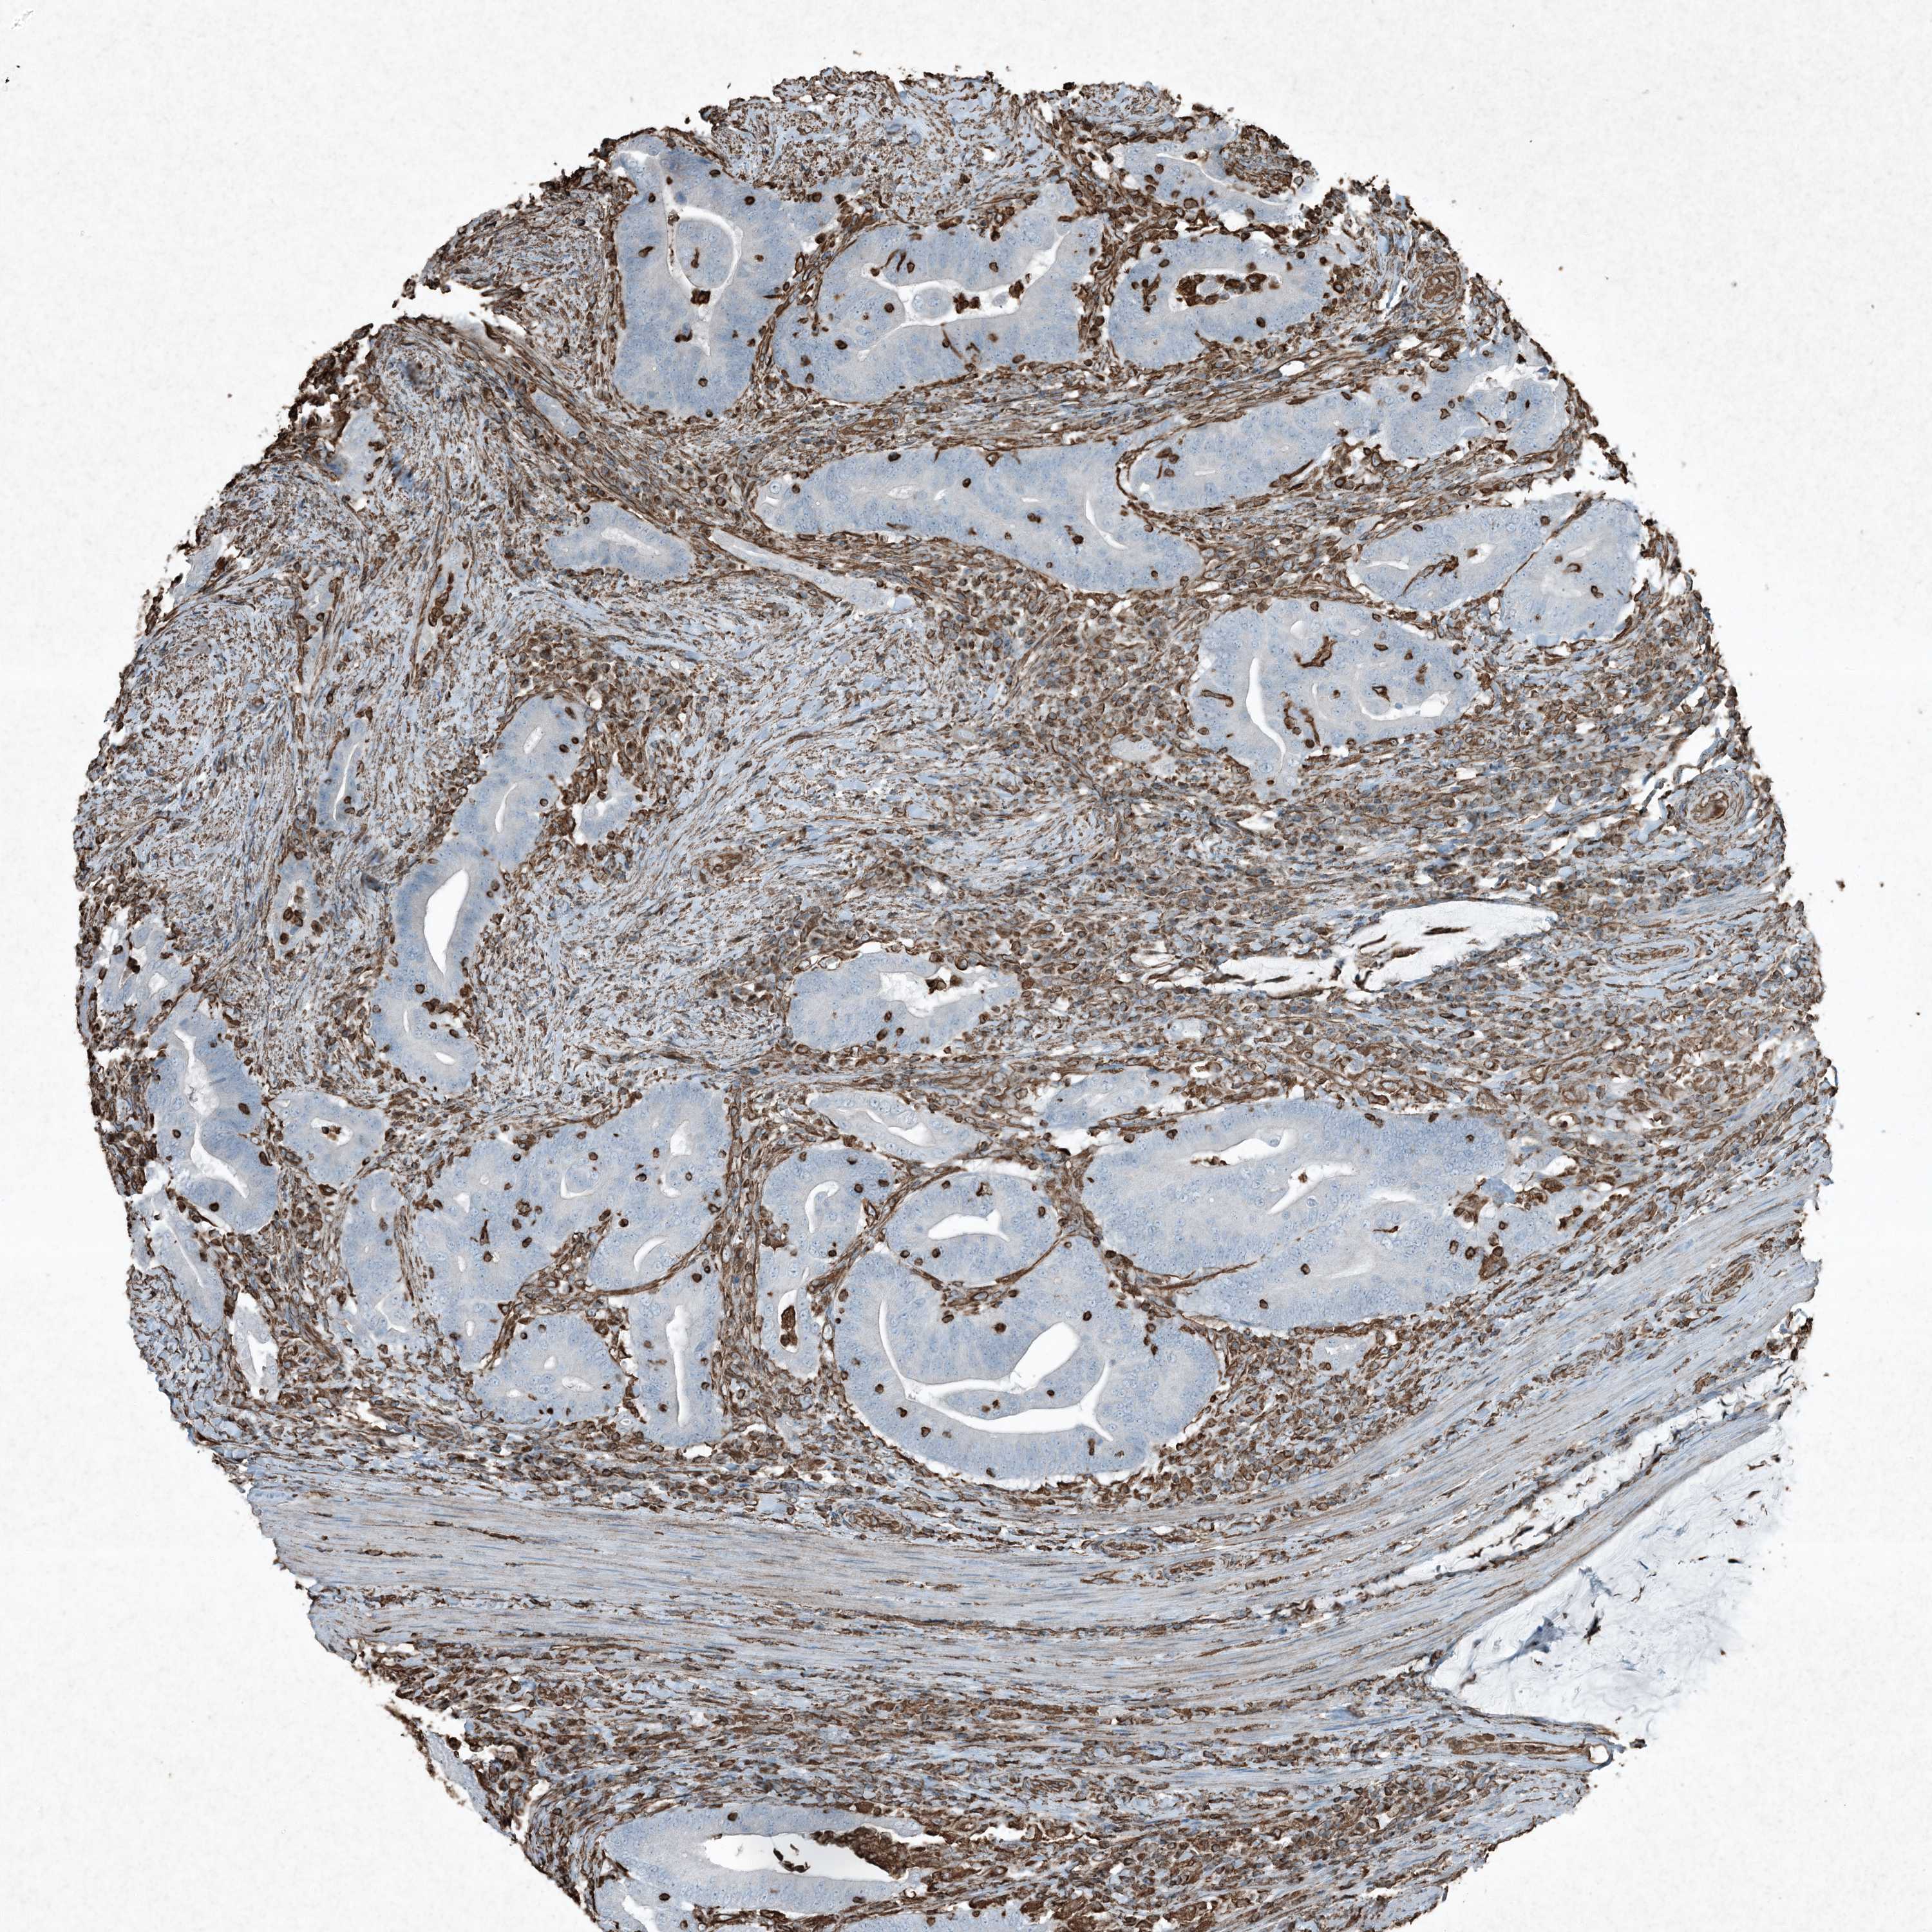

CANCER COLORECTAL CANCER Show tissue menu

Colorectal cancer

Human cancer

Colon adenocarcinoma